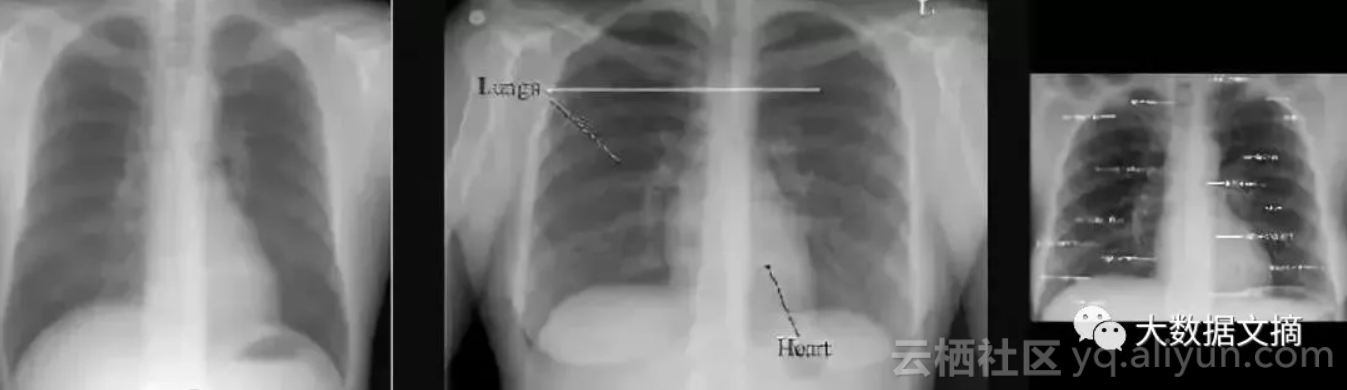

案例的主角是胸部X光图像。

由于设备制造商的不同,胸部X光的图像有可能是水平的,也可能是垂直翻转的。他们可能会倒置像素值,也可能会旋转。问题在于,当你处理一个庞大的数据集(比如说50到100万张图像)的时候,如何在没有医生查看的情况下发现畸变?

上面三幅图中,只有中间的图像存在“黑色边框在两侧”的情况,因而上面这一方案并不实用。

为了说明这一点,我们来看一个来自CXR14的简单例子。在数据集中的正常胸部X射线中,有一些图像经过旋转(这些旋转并未标识在标签中,因此我们不知道哪些是旋转过的)。它们有可能被左右旋转了90度,或180度(颠倒)。

在旋转和竖直胸部X射线之间的差异真的是令人尴尬的简单。

答案是:不难!在视觉上,异常图片与正常图片完全不同。你可以使用一个简单的可视规则,比如说“肩膀应该高于心脏”,然后你就会得到所有正确的结果。鉴于解剖学非常稳定,所有人都有肩膀和心脏,这应该是卷积网络的可以学习的规则。